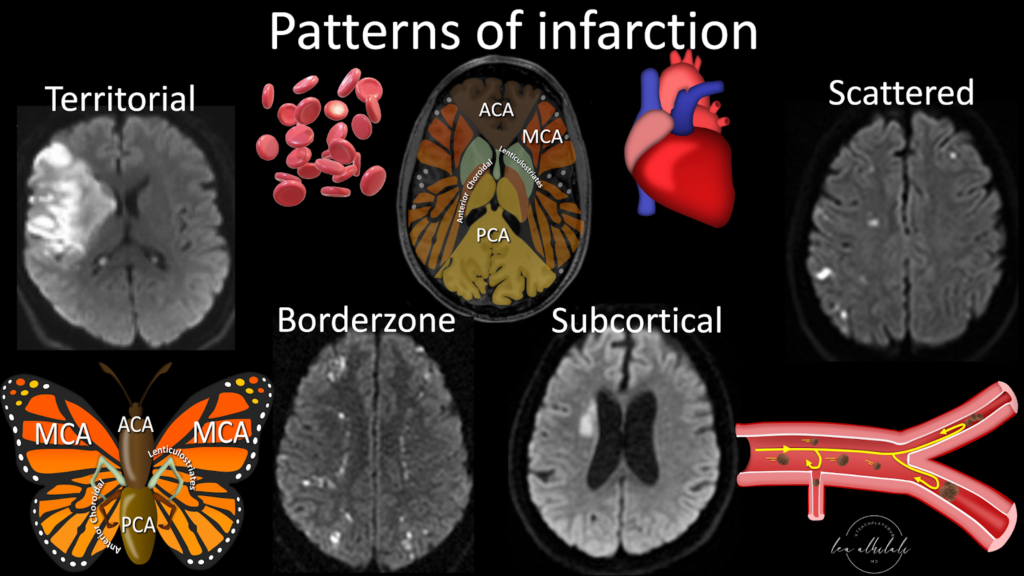

Para el diagnóstico del accidente cerebrovascular isquémico y hemorrágico, se utilizan estudios de imagen de alta calidad, como lo son la tomografía y la resonancia magnética transcraneal.

Patrones de infarto cerebral, “ACA, MCA, PCA” hacen referencia a arteria cerebral anterior, media y posterior, que irrigan el encéfalo en forma de “mariposa”.